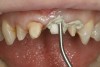

Fig 17. The “H” abutment placed and the seating verified. Aluminum chloride/clay retraction paste was placed into the sulcus before master cast impressions.

Figure 17

The provisional crowns and provisional abutment were removed, and the “H” abutment was placed and hand-torqued. A radiograph was taken to ensure complete seating and intimate adaptation between the abutment and implant body. The abutment was then torqued using a torque driver following manufacturer’s recommendations. The implant screw hole was filled using a light-cure flexible provisional material placed into the titanium sleeve, followed by a nanohybrid composite resin to match the shade of the abutment, and then light-polymerized. The lateral incisors were prepared for full-coverage all-ceramic crowns to optimize esthetics and function. To capture an accurate representation of the sulcus with the impression material, a 15% aluminum chloride/Kaolin clay retraction paste was injected into the sulcus and allowed to remain for 2 minutes to atraumatically retract the gingival tissues around the margins (Figure 17), and then was rinsed thoroughly. A full-arch polyvinyl impression was taken, followed by an anterior bite registration. The previously taken opposing model was used to mount the maxillary model to the articulator and, thus, a new mandibular impression was not needed.